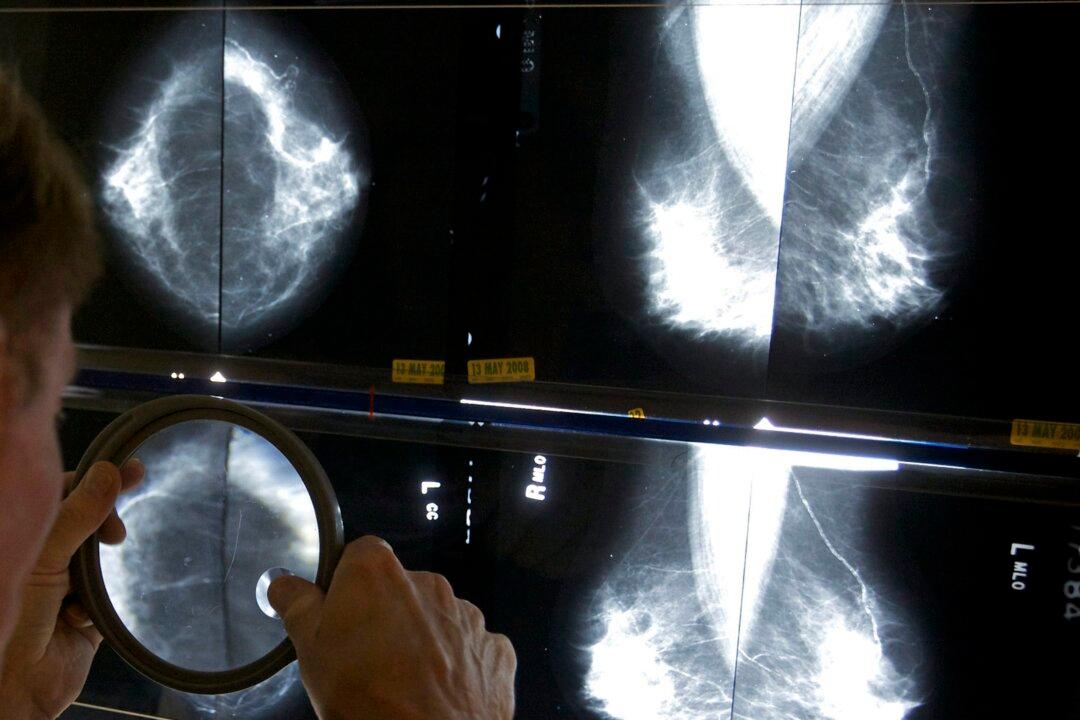

Cancer cases and deaths are expected to increase in 2024, according to a recent study from the Canadian Medical Association Journal.

“Although the overall incidence of cancer and associated mortality are declining, new cases and deaths in Canada are expected to increase in 2024, largely because of the growing and aging population,” said the May 13 study “Projected Estimates of Cancer in Canada in 2024.”